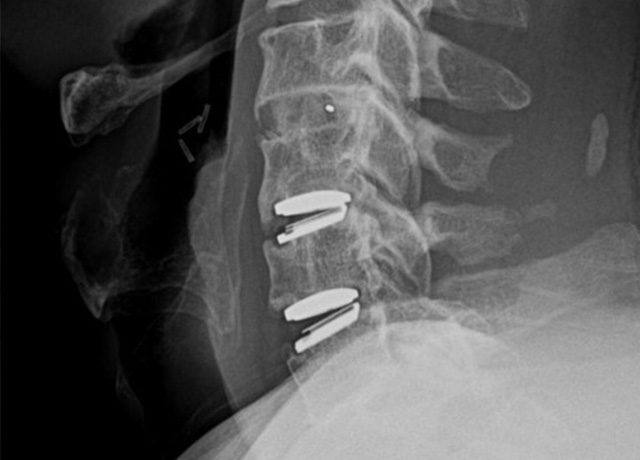

경추 인공디스크 치환술

(Cervical Artificial Disc Replacement)